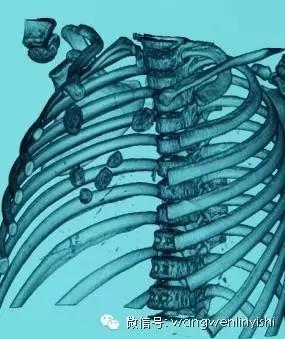

(胸骨上半裂开)

(三维重建图)